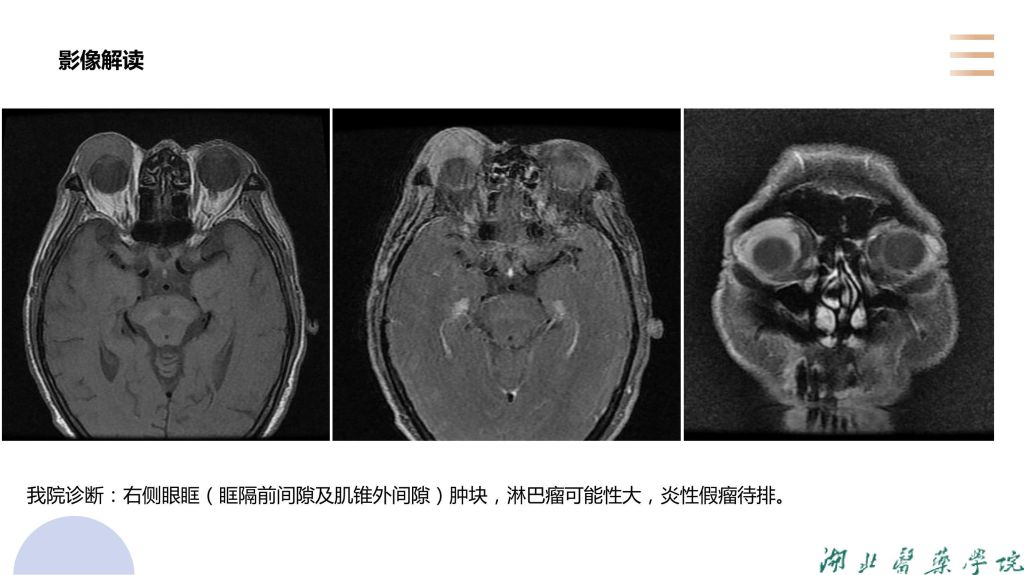

病例分析-眼眶淋巴瘤